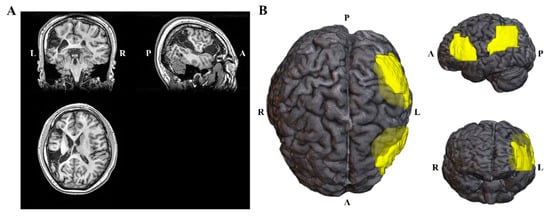

2. Case Presentation